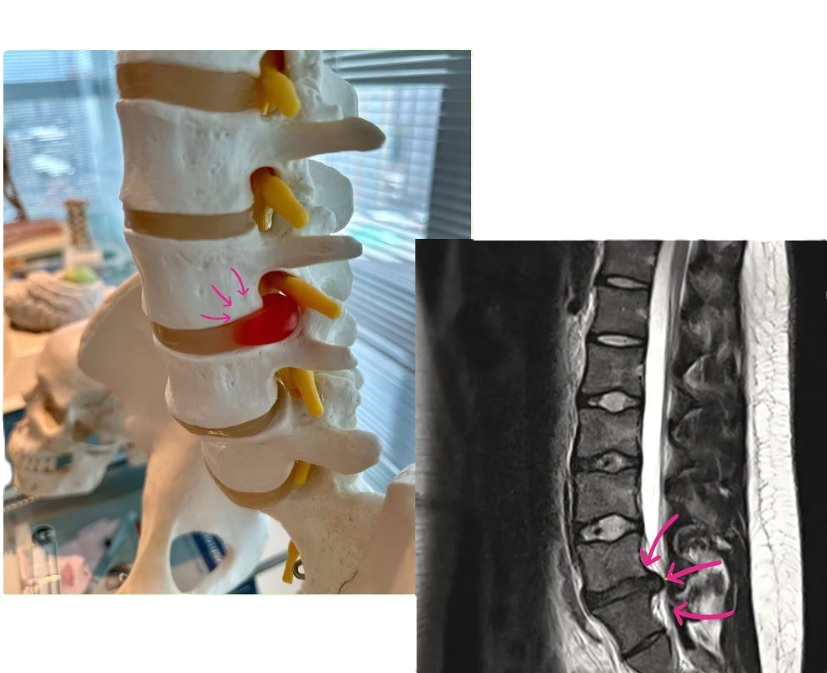

A coluna vertebral lombar suporta grande parte do peso corporal e permite movimentos essenciais do dia a dia. Os discos intervertebrais funcionam como amortecedores entre as vértebras. Quando o anel fibroso externo enfraquece ou se rompe, o núcleo gelatinoso central pode se deslocar (herniar), comprimindo raízes nervosas e gerando inflamação e dor.

Ressonância Magnética (RM): exame de escolha, mostra com precisão a hérnia, o grau de compressão nervosa e o nível afetado. Essencial para planejar procedimentos minimamente invasivos.